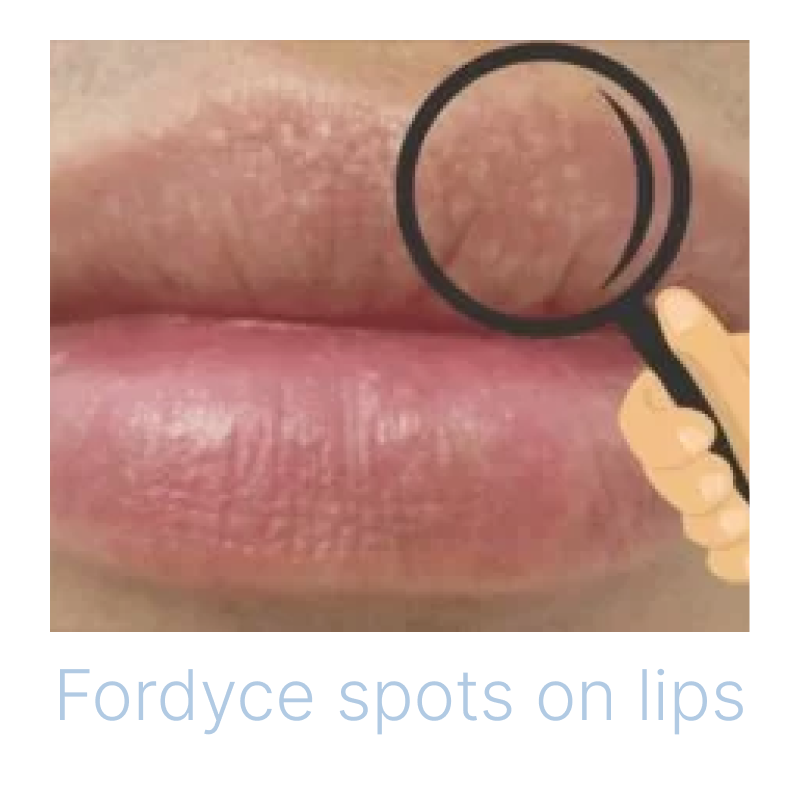

唇のブツブツ:フォアダイスの原因・治し方・予防等について - 美容外科船橋中央クリニック&青山セレスクリニック。

唇のブツブツ:フォアダイスの原因・治し方・予防等について - 美容外科船橋中央クリニック&青山セレスクリニック。

唇のブツブツ:フォアダイスの原因・治し方・予防等について - 美容外科船橋中央クリニック&青山セレスクリニック。

30代男性 唇フォアダイス 電気凝固術- 症例写真 - 美容整形、美容外科なら聖心美容クリニック。

唇のブツブツ:フォアダイスの原因・治し方・予防等について - 美容外科船橋中央クリニック&青山セレスクリニック。